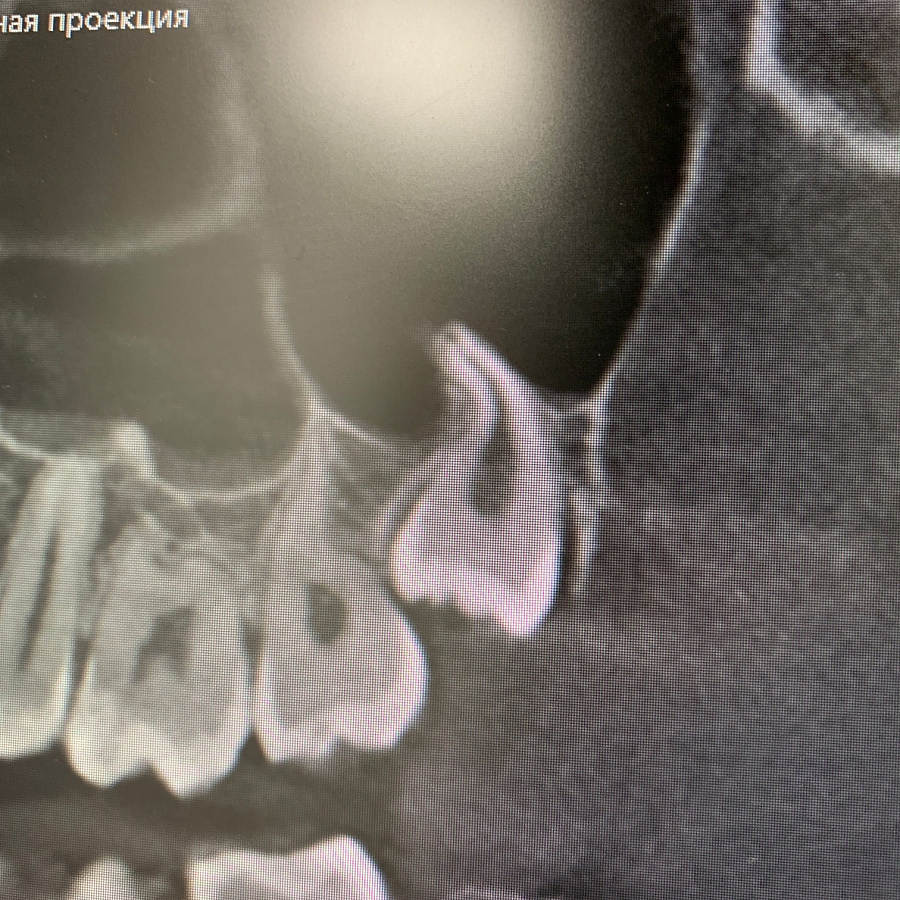

Удаление ретинированного дистопированного зуба мудрости на верхней челюсти слева.

Сложность данного кейса в том, что восьмой зуб упирается под углом в сторону седьмого зуба. Зуб удален полностью, дискомфорт пациент не испытывает.